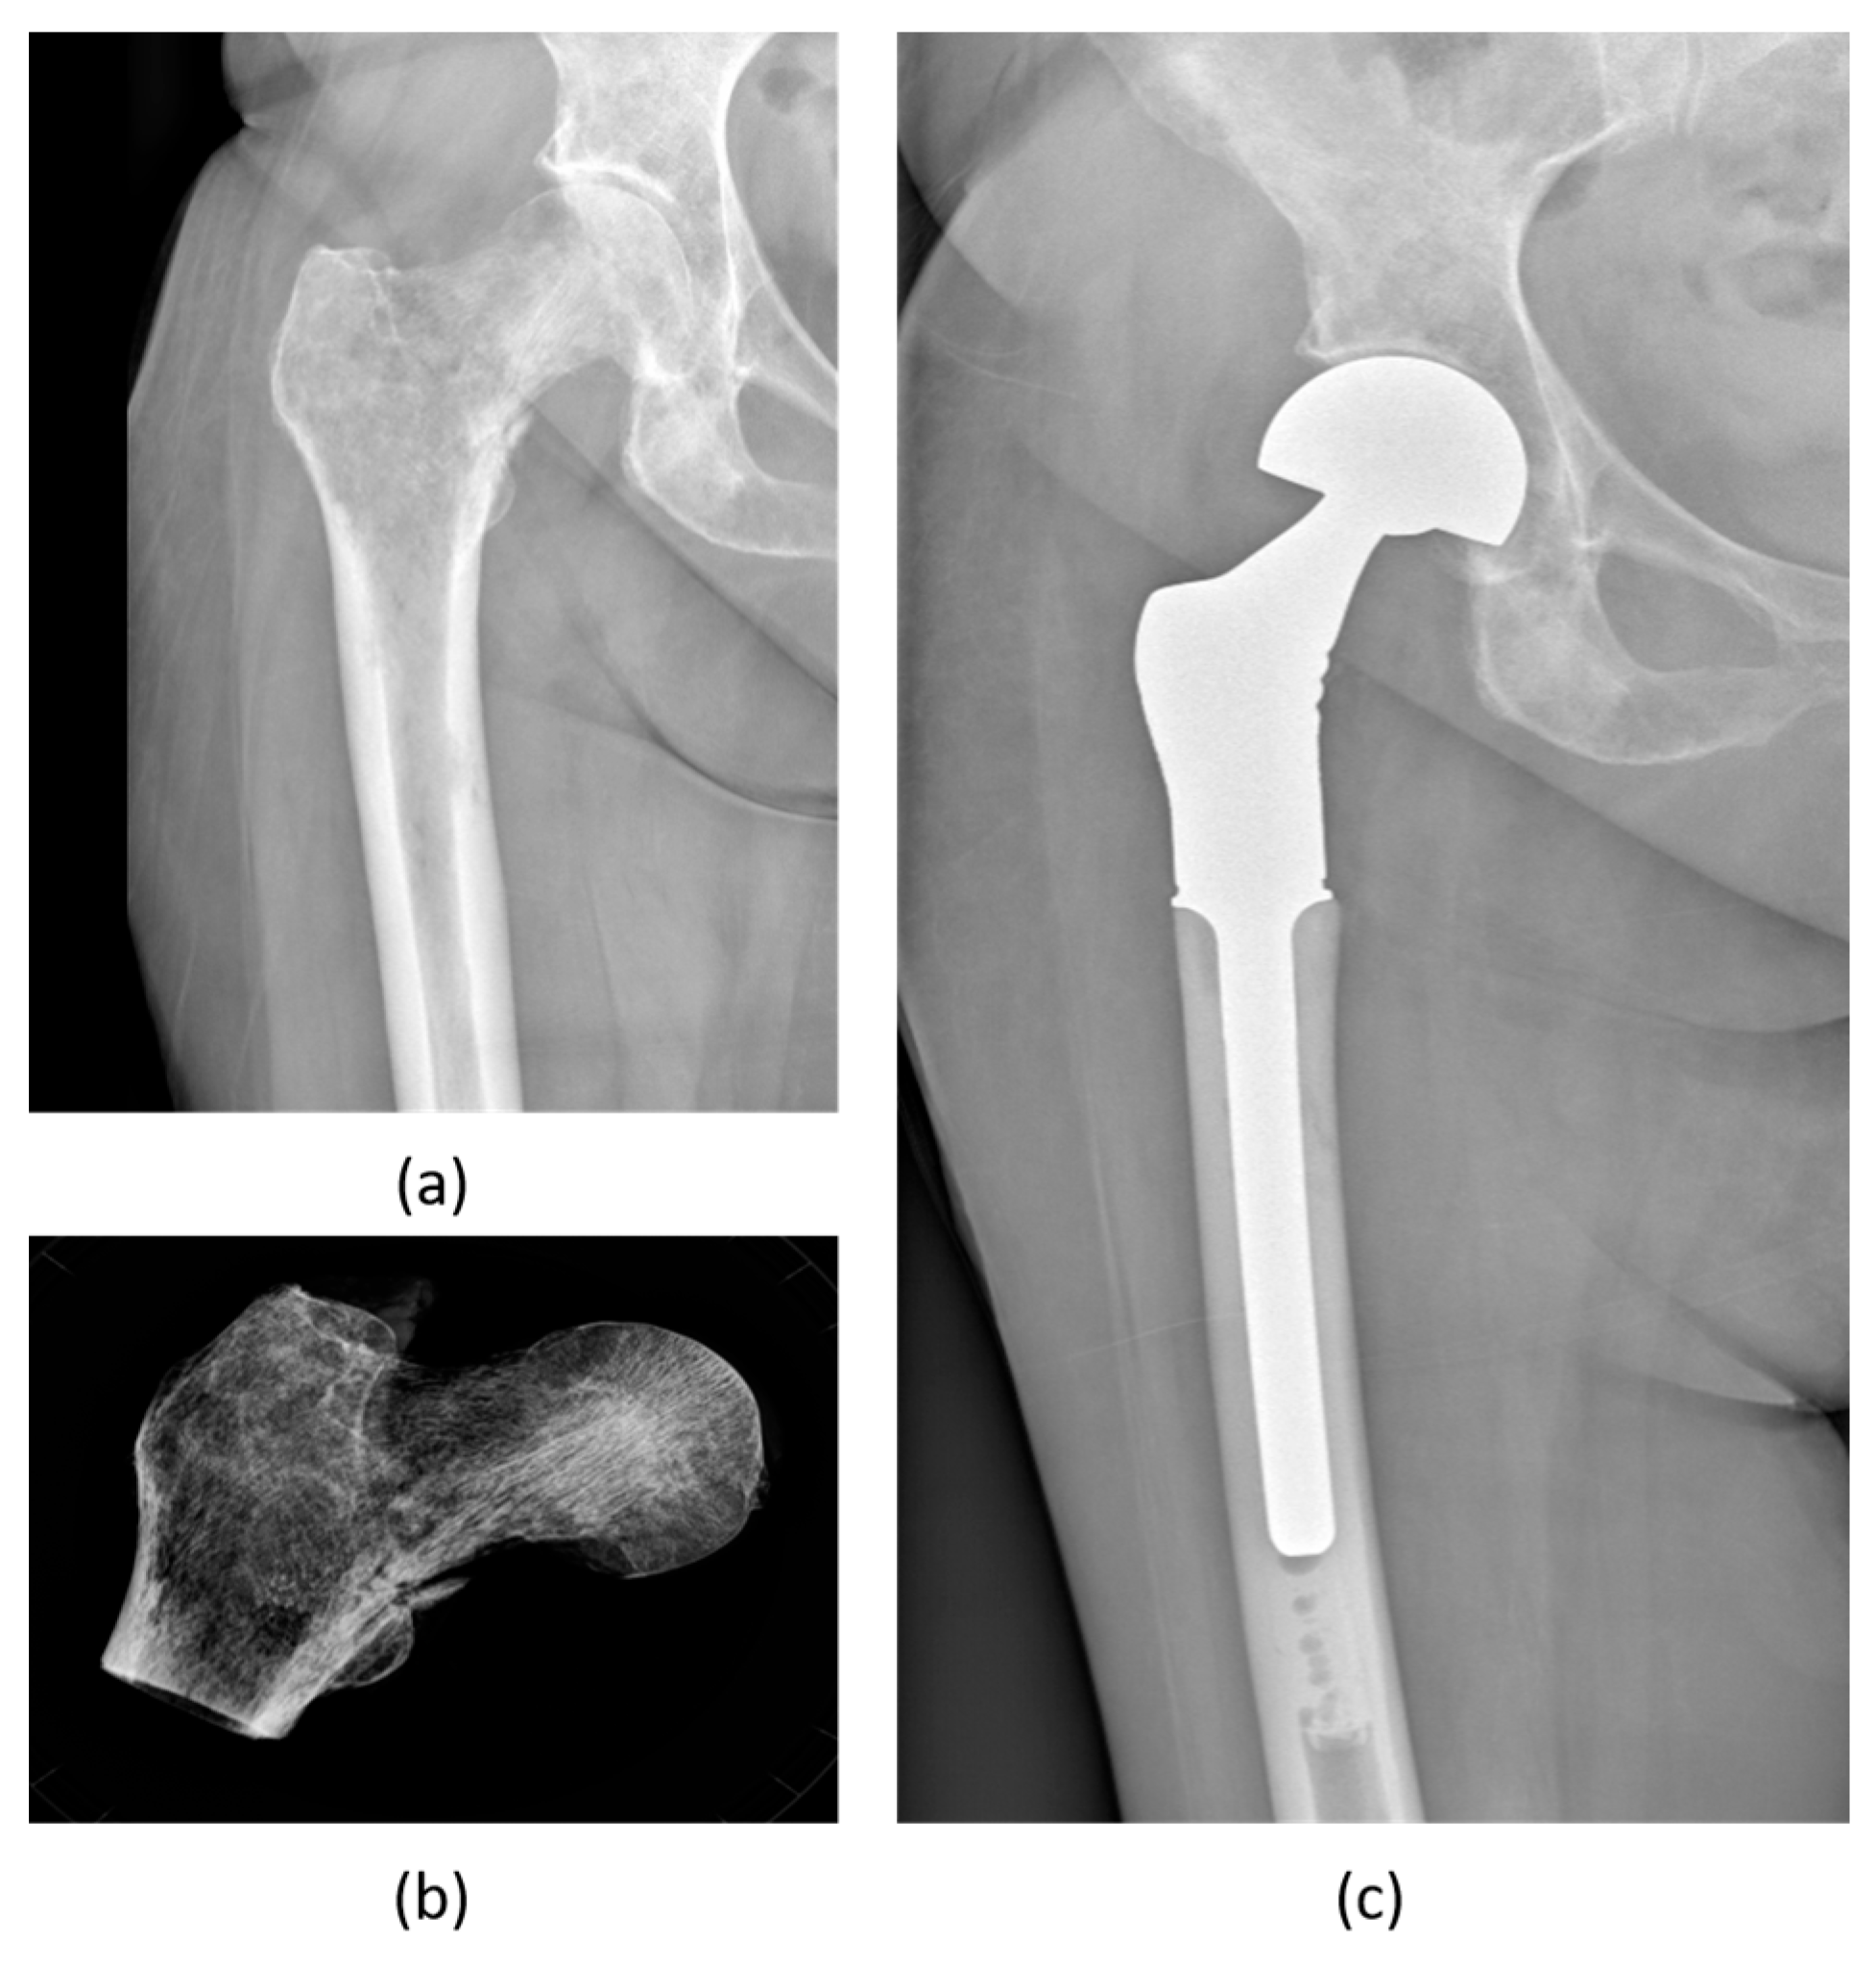

Injuries represent another intriguing chapter of sex- and gender-specific orthopedics. According to a recently published current concepts review [44], encompassing 28 studies, sex- and gender-related differences could be identified in several key areas related to the management of total hip arthroplasty: namely, (i) the choice of surgical approach, use of robotic surgery, considerations of scar appearance, and selection of implants; (ii) outcomes and complications following surgery; (iii) the impact on sexual activity post-total hip arthroplasty; and (iv) psychological well-being and daily functional capabilities. Sex- and gender-specific analyses revealed that female patients may require more tailored considerations during the preoperative, operative, and post-operative stages to enhance clinical and functional results, minimize the likelihood of complications, and ensure patient satisfaction. The success of the total hip arthroplasty procedures was found to be significantly affected by factors related to sex and gender, which necessitates a careful evaluation and the adoption of specifically devised interventional strategies in surgical patients to enhance their satisfaction with the surgery’s outcomes and lower the incidence of sex-differentiated post-operative complications.